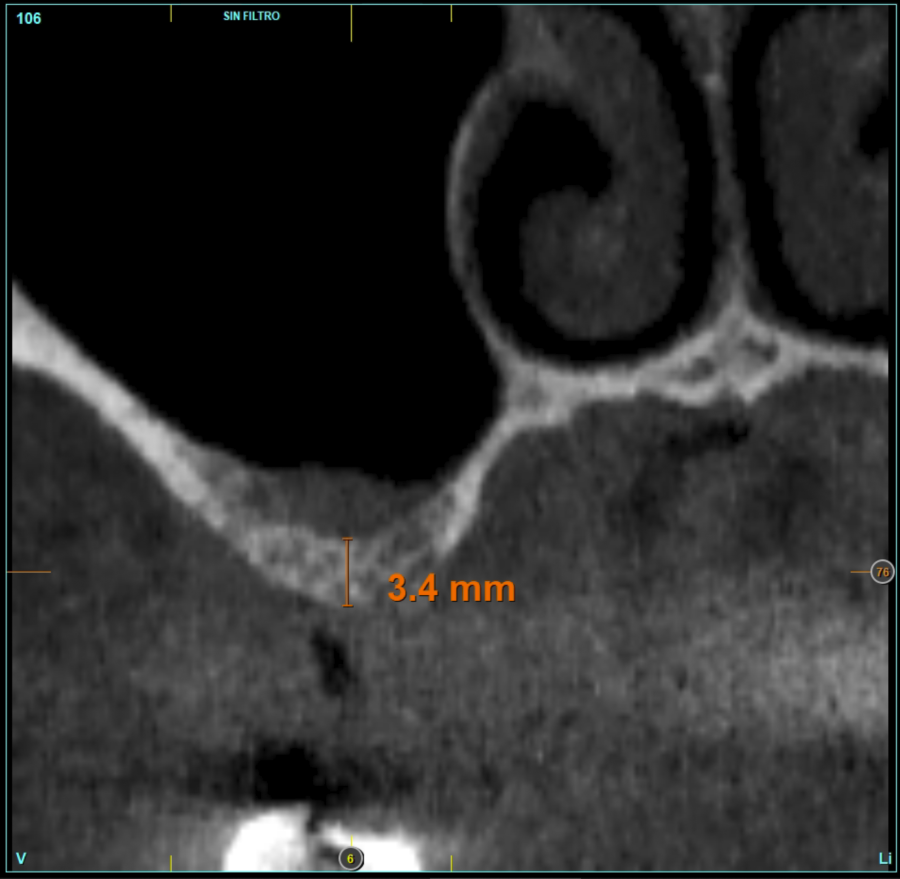

In all cases, a diagnosis was made based on study models, intraoral examination of the patient and performing a Cone-beam analysed using the specific BTI-Scan 3 software (Biotechnology Institute, Vitoria, Alava, Spain).

Patients attend subsequent check-ups performing a control Cone-Beam after 5 months (before loading the implant) and after one year of the load, performing a new measurement in these images to analyse the bone gain and the maintenance of the same. In these check-ups, data are collected on prosthetic complications or crestal bone loss in these patients, as well as possible failures.

The mean height of the residual bone volume was 3.1 mm (+/- 0.3 mm with a range of 3-4 mm). In all cases, transcrestal sinus elevation was performed, with particulate autologous bone obtained from milling the neo alveolus generation zone for implant insertion, being the average of this elevation above the apex of the implant of 2.8 mm (+/- 0.99 range 1.9 -5 mm). In the CT control scan after one year of inserting the studied implants, the bone gain achieved was maintained, no decrease in the volume gained was observed, only three cases showed a decrease of between 0.4 and 0.5 mm of the initial volume at the end (Table).

Figures 2-19 show one of the cases included in the study.

Material and method. A retrospective study has been carried out in patients in whom extra-short implants (4.5 and 5.5 mm length) were inserted directly by transcrestal elevation with residual ridges between 2 and 3 mm. The implant was the analysis unit for the descriptive statistics regarding location, implant dimensions, and radiographic measurements. The patient was the measurement unit for the analysis of age, sex and medical history. The main variable was the gain in height over the apex of the implant after 6 months of the surgery and one year after the load comparing both measurements and as secondary variables the biological complications and the implant failure were recorded.